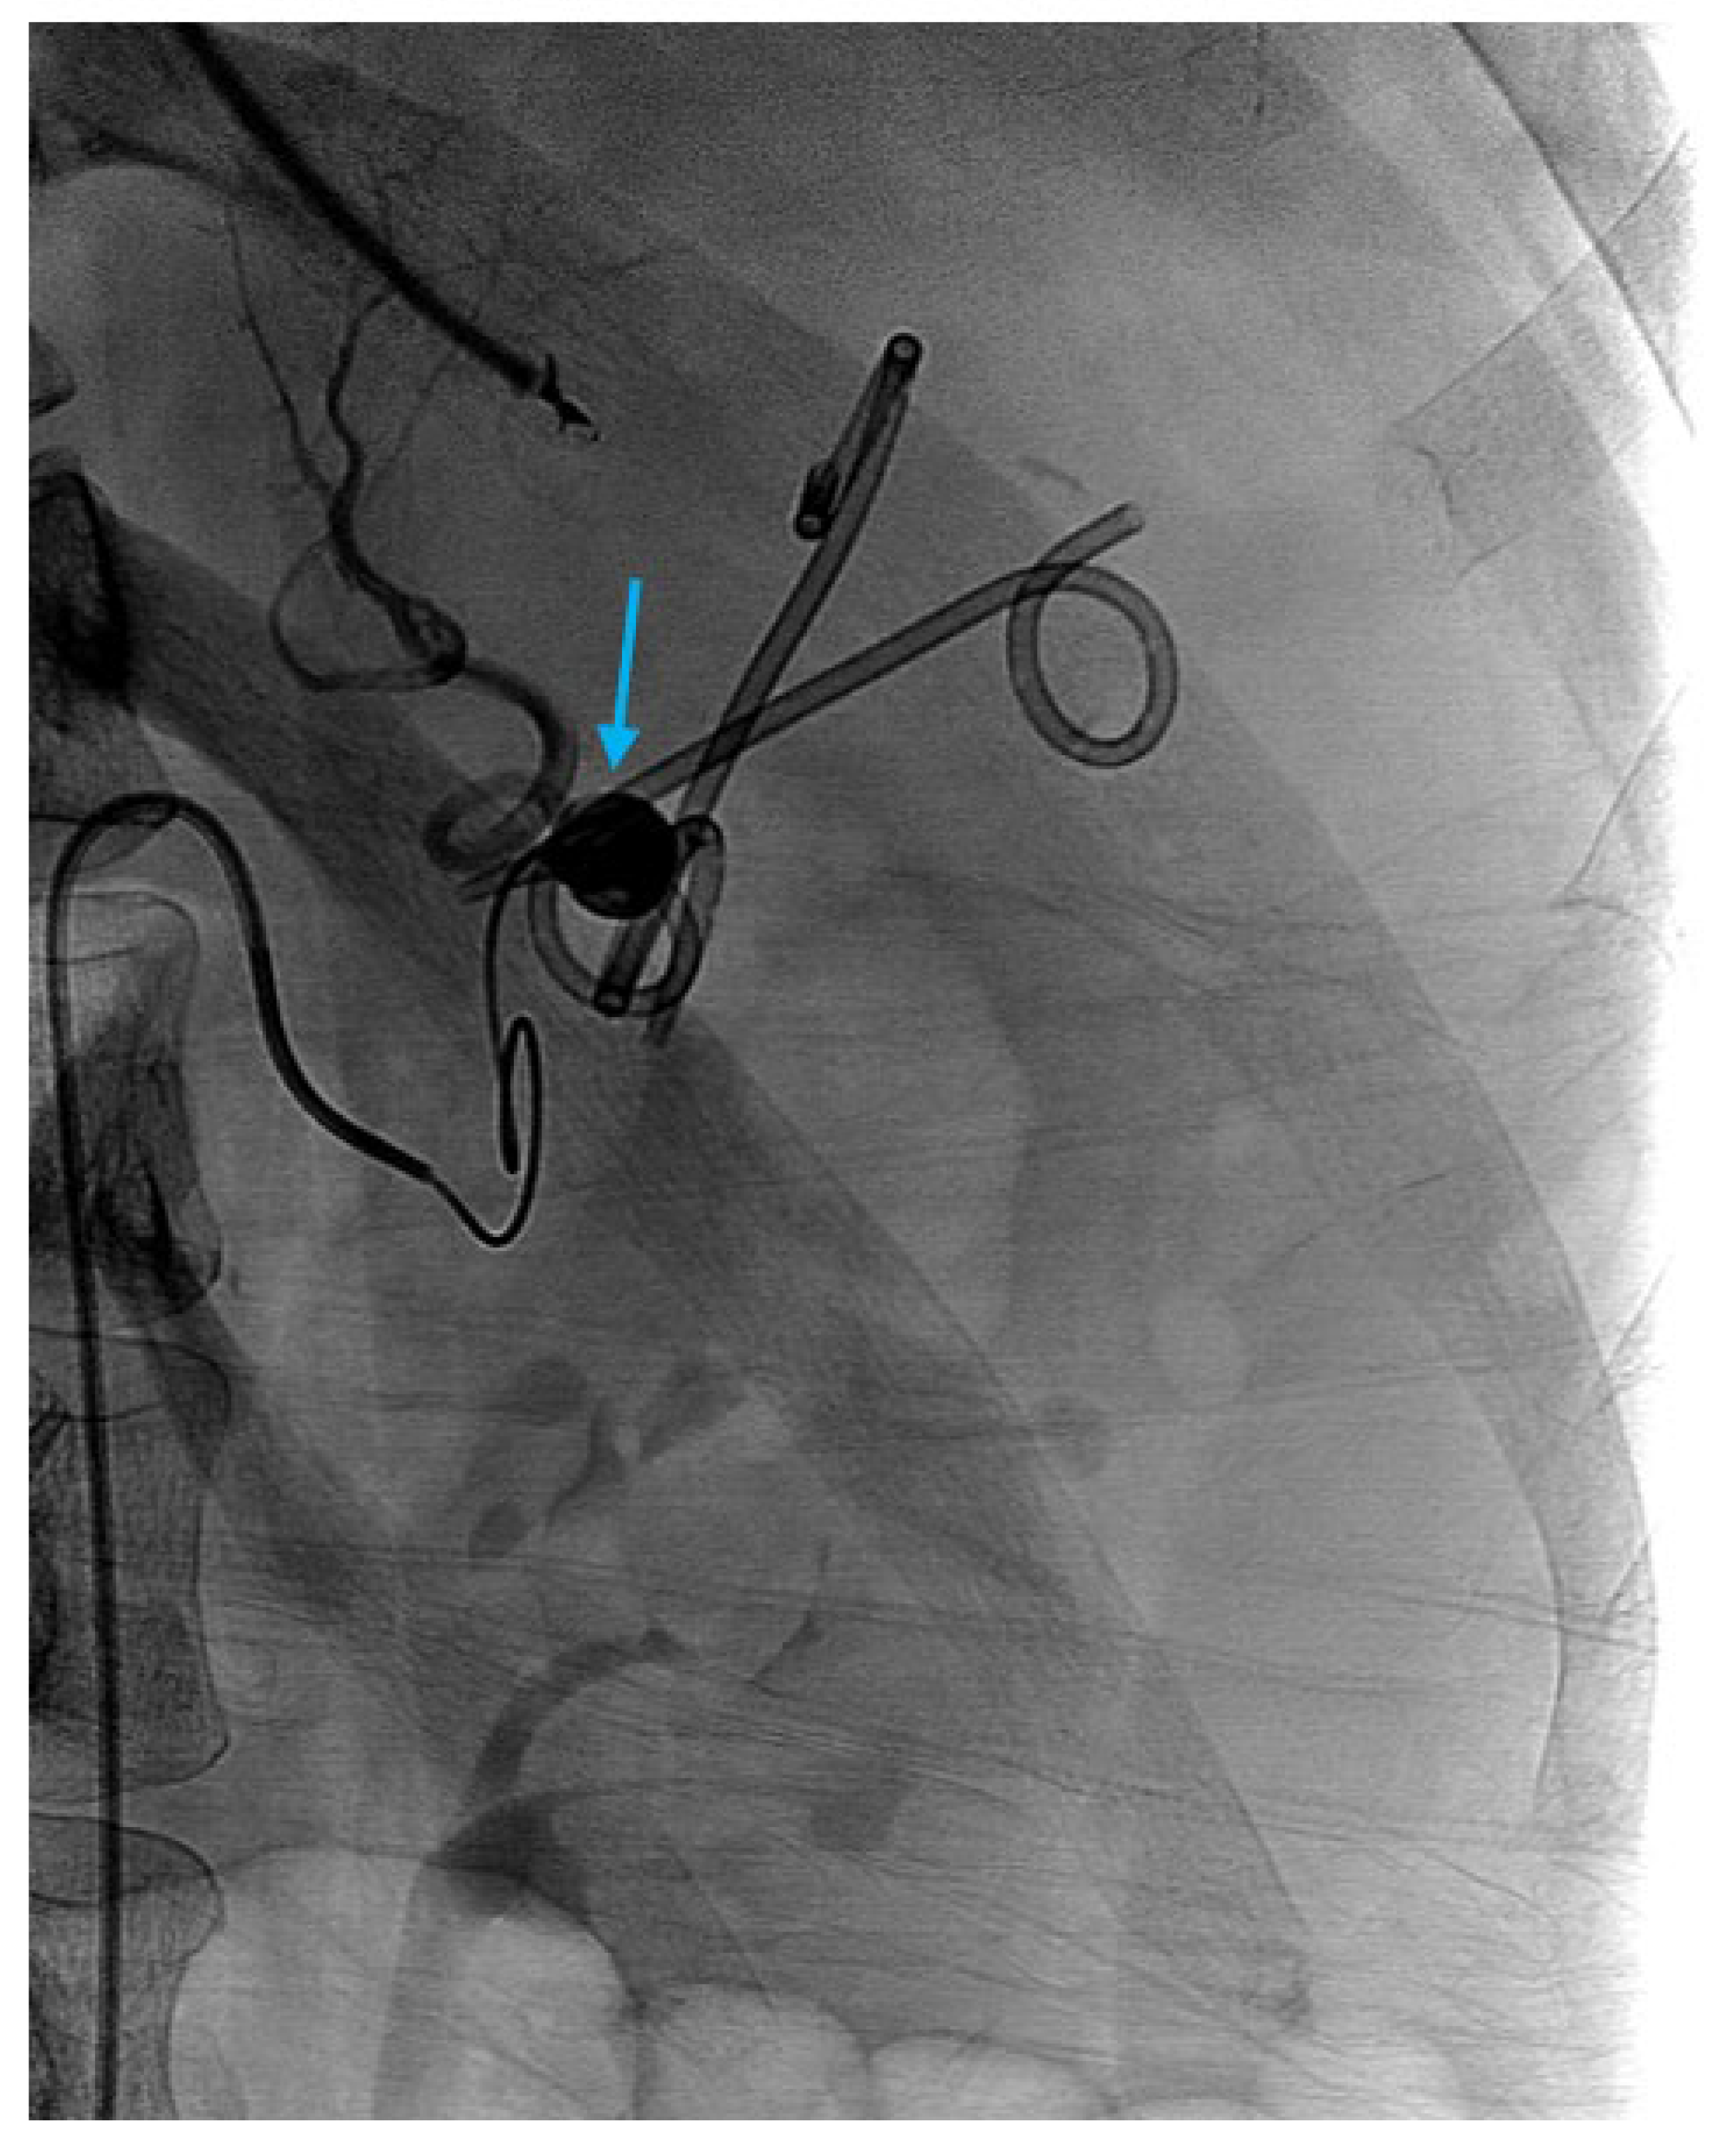

2.7. Interventional Radiology-Guided Embolization of Pseudoaneurysms